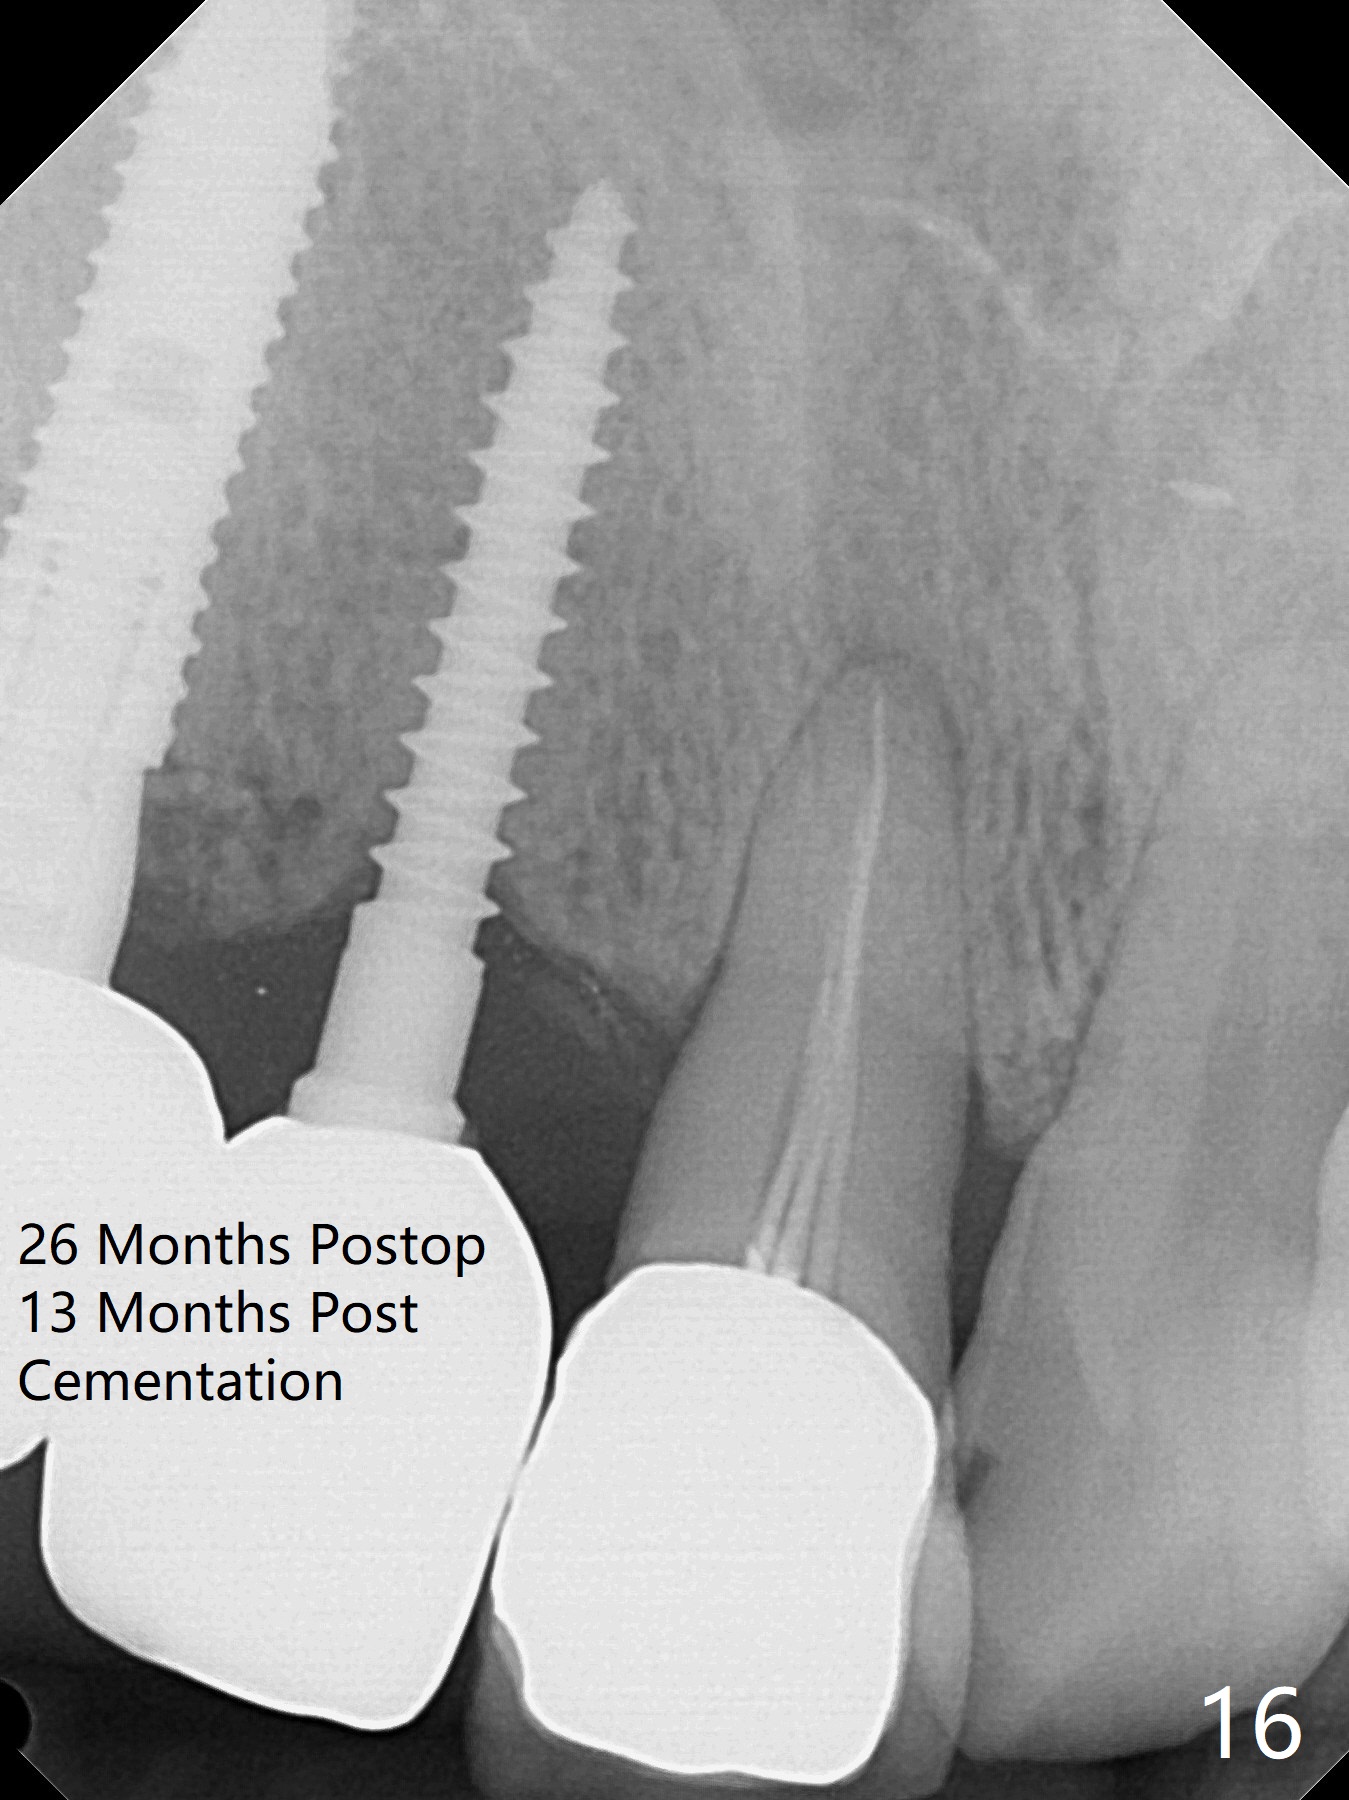

Since the ridge at #7 is ~ 4 mm, a 2.5x14 mm 1-piece implant is placed (Fig.8) after 1.2 mm (Fig.7), and 1.5 mm drills at 12 mm and 2 mm drill at 8 mm.  Later the implant is placed deeper (Fig.10).  There is no bone loss 7 or 12 months postop, respectively (Fig.11,12).  After Diode gingivectomy, there is papillary formation (Fig.13).  No provisional is provided after impression (with the abutment torqued at #6) for oral hygiene.  With access holes at #6 and 7, crowns are bonded with minimal residual cement (Fig.14 <, which is removed later).  There is no hard (Fig.15,16) or soft (Fig.17 *) atrophy 26 months postop, i.e., 13 months post cementation, due to the presence of socket shield (Fig.15 <, as compared to Fig.1).  In fact the tooth #8 has mobility and fremitus (short root/poor crown/root ratio, Fig.16); occlusal adjustment is done 13 months post cementation.  The crown is dislodged 2 years 1 month post cementation; a prefabricated post is being tried in (Fig.18).  There is no atrophy, bone loss or infection at #6 (with socket sheath (*)) or 7 two years 5 months post cementation (Fig.20-27).